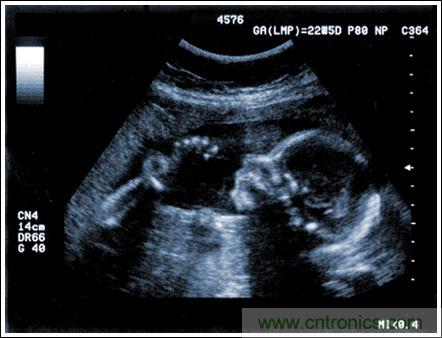

超聲成像系統(tǒng)及主要子功能電子元件的設(shè)計(jì)考慮

【導(dǎo)讀】該應(yīng)用筆記介紹了超聲成像系統(tǒng)的設(shè)計(jì)考慮,討論成像系統(tǒng)的小型化、低成本和便攜化的發(fā)展趨勢,同時(shí)闡述了在小型系統(tǒng)中實(shí)現(xiàn)大型車載系統(tǒng)所具備的性能和診斷能力的重要條件。文章探討了超聲系統(tǒng)的子功能以及對電子元件的要求,重點(diǎn)討論了傳感器、高壓復(fù)用器、高壓發(fā)射機(jī)、成像通道接收機(jī)、數(shù)字波束成形、波束成形數(shù)字信號處理及顯示處理等。

通過發(fā)射超聲能量進(jìn)入人體,接收并處理返回的反射信號,相控陣超聲系統(tǒng)可以生成體內(nèi)器官和結(jié)構(gòu)的圖像,映射血液流動和組織運(yùn)動,同時(shí)提供高準(zhǔn)確度的血流速度信息。傳統(tǒng)設(shè)計(jì)中,構(gòu)建這樣的成像系統(tǒng)需要大量的高性能相控陣發(fā)射器和接收器,使得車載設(shè)備體積龐大且價(jià)格昂貴。近年來,隨著集成工藝的進(jìn)步,設(shè)計(jì)人員能夠獲得小尺寸、低成本而且高度便攜的成像系統(tǒng)方案,并可達(dá)到接近大型成像設(shè)備的性能指標(biāo)。而新的設(shè)計(jì)挑戰(zhàn)依然存在,即在進(jìn)一步提高方案集成度的同時(shí)提高系統(tǒng)性能和診斷能力。